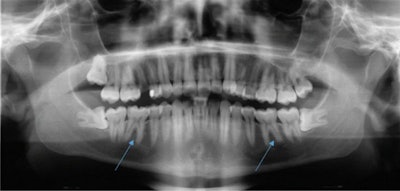

The patient's routine x-ray taken by a primary dentist in January 2019 reveals that tooth #36 and #46 showed no signs of apical osteolysis before the intense bruxism started. The teeth also did not show visible signs of caries or fillings. All images courtesy of Gund et al. Licensed by CC BY 4.0.A percussion test was negative, and the exam and imaging revealed no anomalies, pulp calcifications, or formation defects of the hard tooth tissue. Also, there was no external resorption, root canal, or pulp chamber perforation, according to the report.